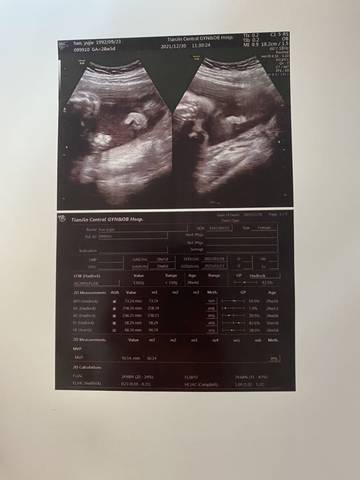

孕29周 超声提示右耳廓形态异常,怎么办 严重么 有没有会看超声单子的

journal_insert_pic_1689136777

你好,如果你这个看的不太清楚的话,应该是要做一个检查吧,你可以先听医生的意见就好了